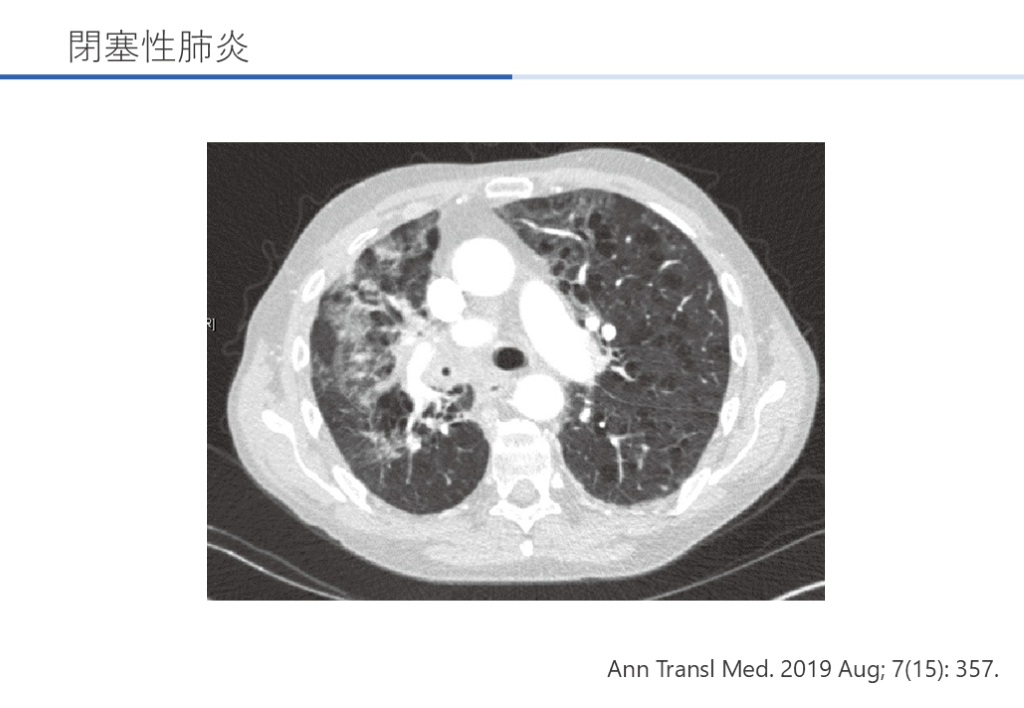

Ann Transl Med. 2019 Aug; 7(15): 357. 閉塞性肺炎

閉塞性肺炎 Ann Transl Med. 2019 Aug; 7(15): 357.

閉塞性肺炎 臨床症状と特徴 難治性、再発性の肺炎の際に想起する。 小細胞癌や扁平上皮癌等の中枢側の癌に多い。 診断と検査 感染は閉塞の遠位にあり、微生物の入手が困難。 造影CTは閉塞の特定に有用。 最終的には気管支鏡が必要となる。 Ann Transl Med. 2019 Aug; 7(15): 357.